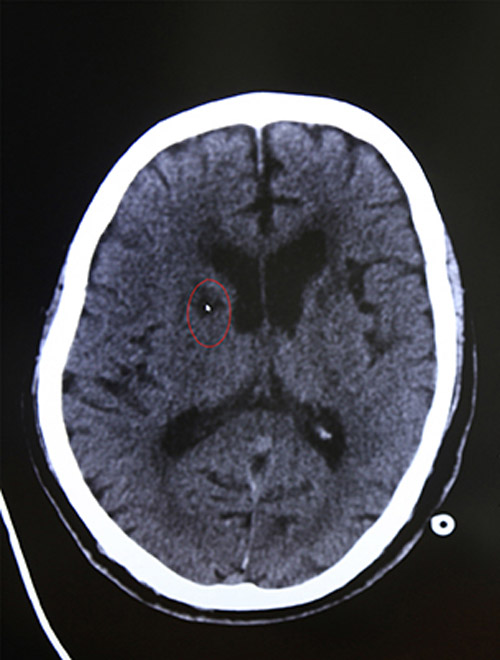

急诊CT示:排除脑出血

16:44 影像科3分钟出报告,CT报告显示:排除脑出血。为进一步查看脑血管情况,又迅速完成了颅脑血管磁共振检查,结果显示:脑梗塞。